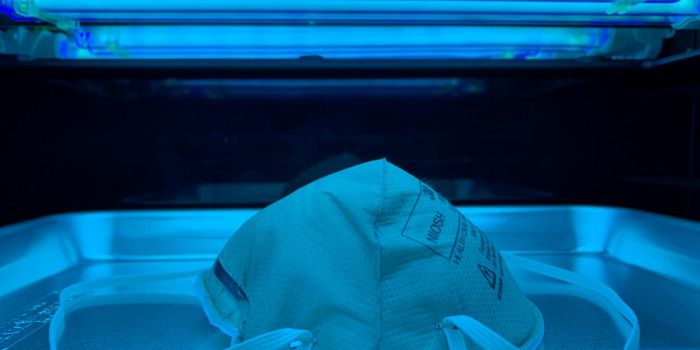

NOV 10, 2024Clinical & Molecular DXThe FDA has a site where people can check the expiration dates, and potential extensions on those dates, for at-home COV ...